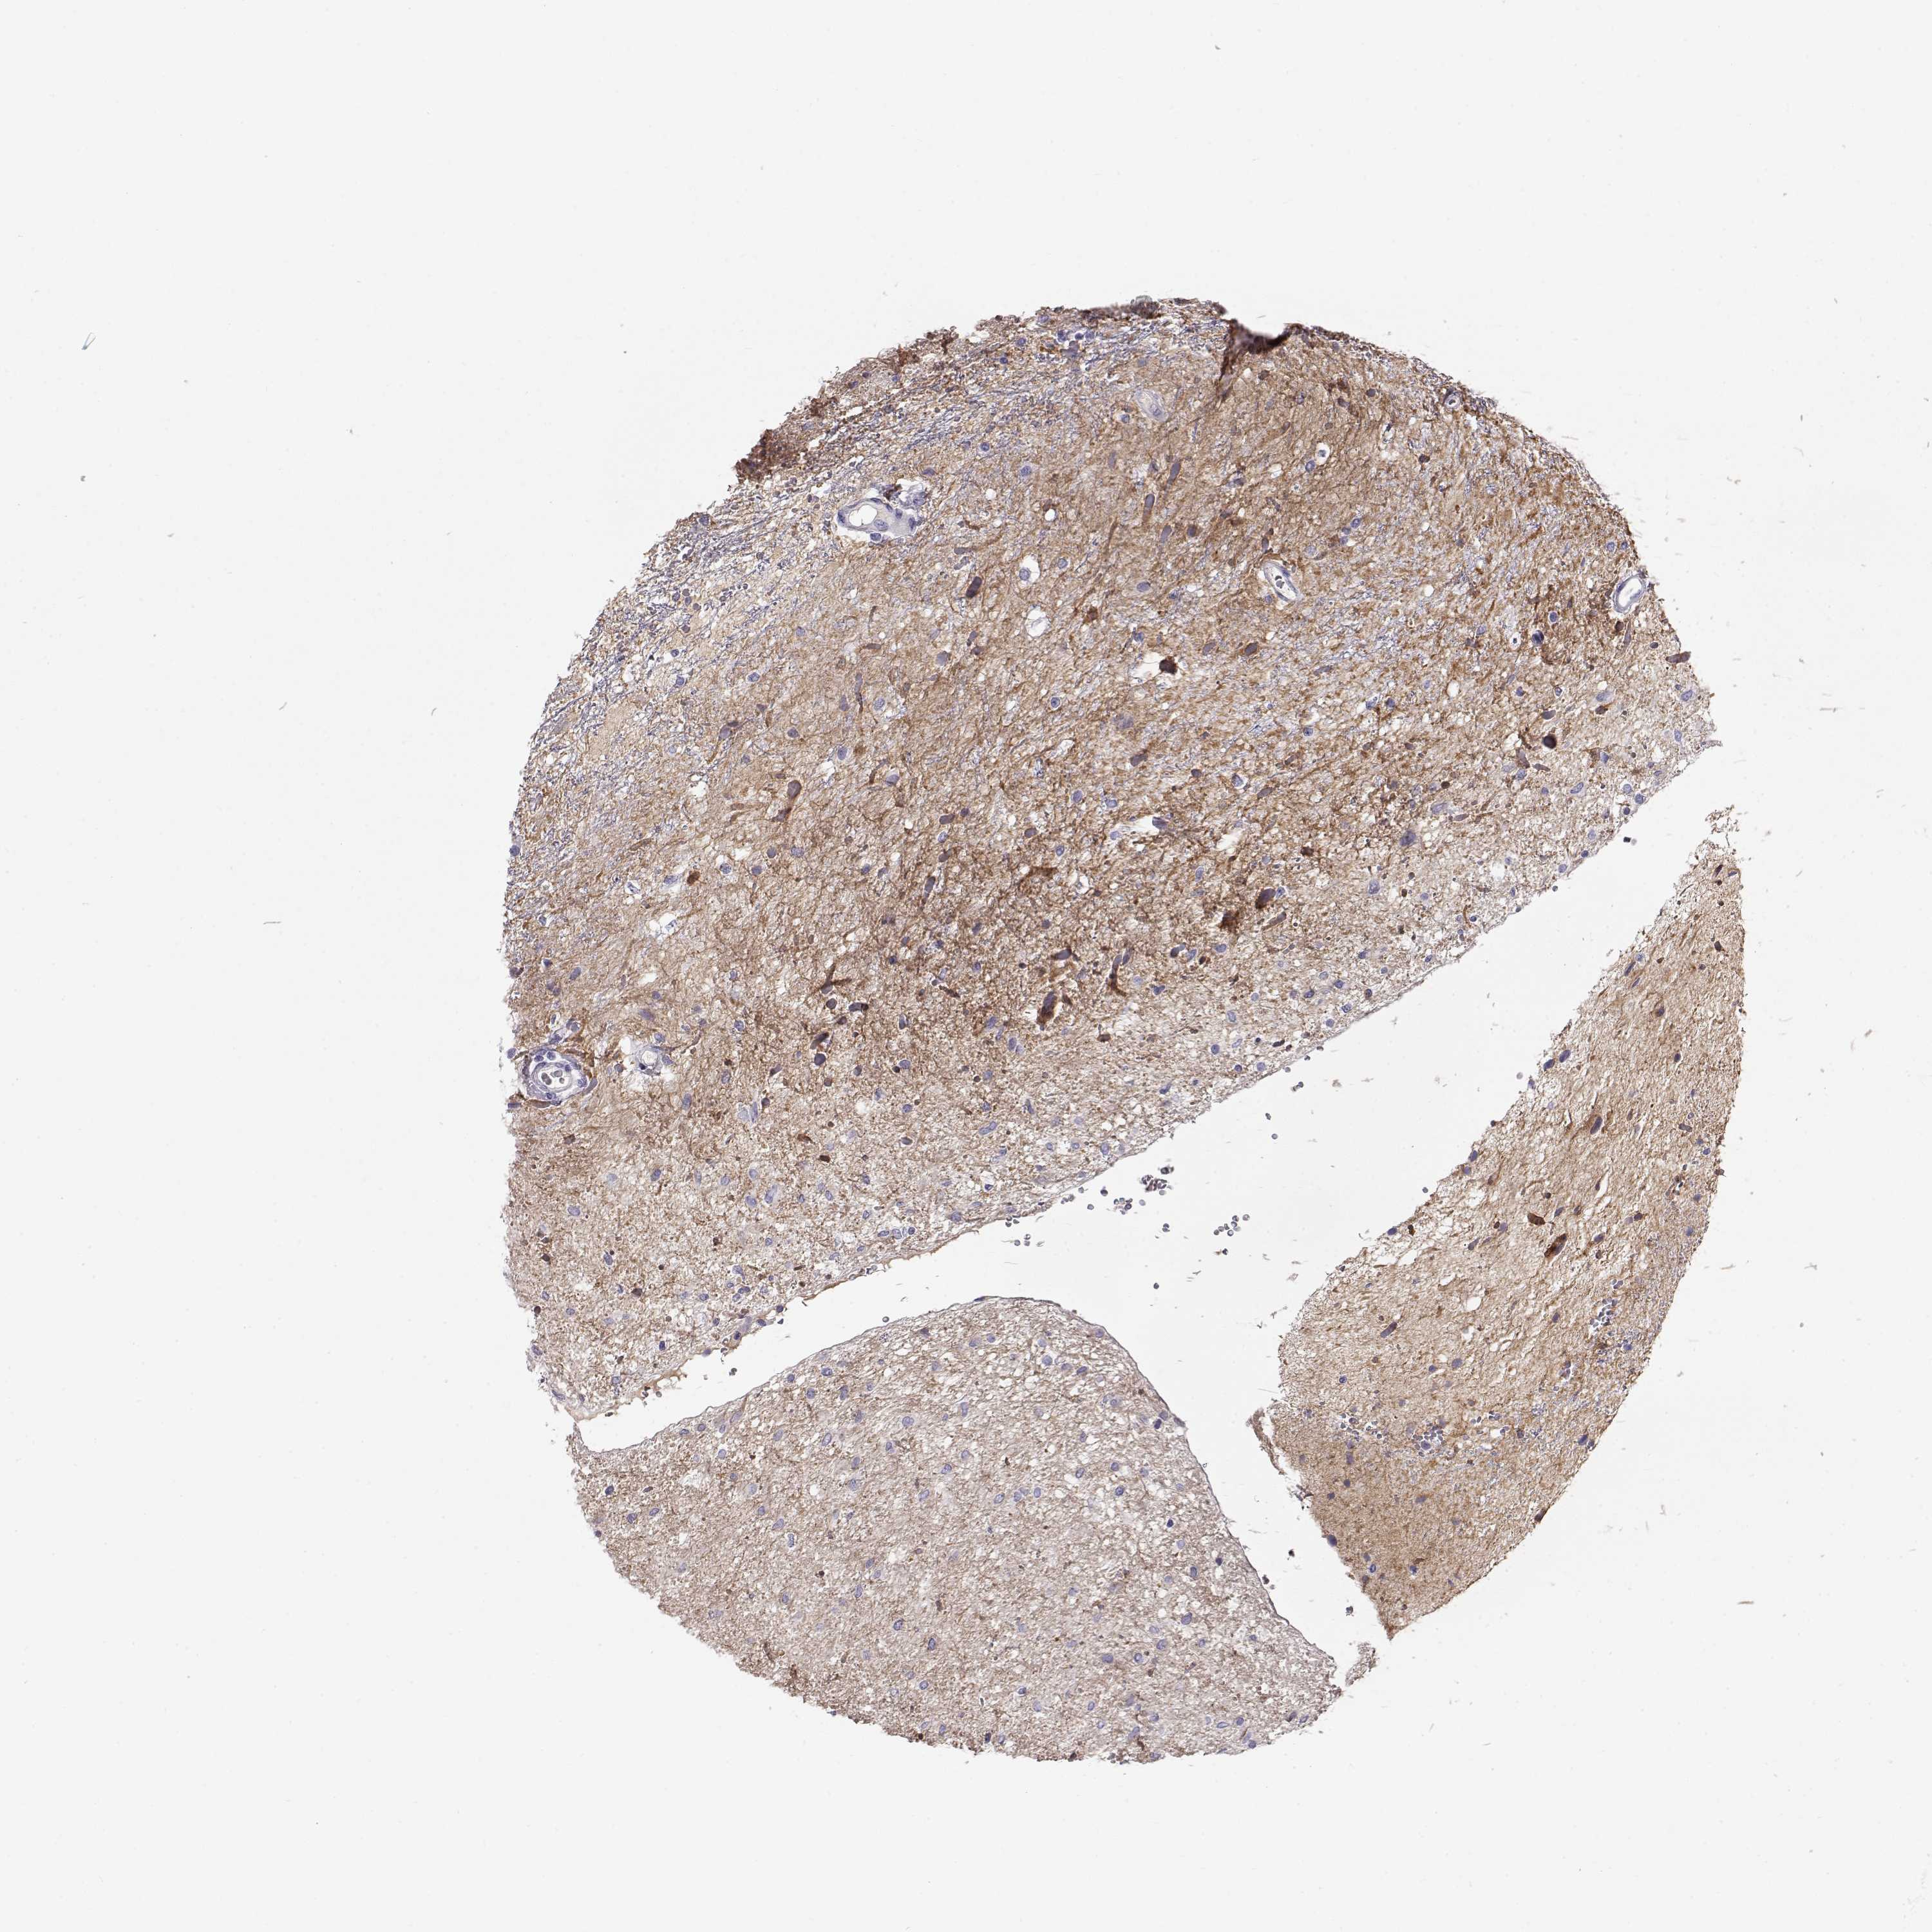

GLIOMA - Protein expressioni

A mouse-over function shows sample information and annotation data. Click on an image to view it in a full screen mode. Samples can be filtered based on level of antibody staining by selecting one or several of the following categories: high, medium, low and not detected. The assay and annotation is described here.

Note that samples used for immunohistochemistry by the Human Protein Atlas do not correspond to samples in the TCGA dataset.

Antibody stainingi

Antibody staining in the annotated cell types in the current human tissue is reported as not detected, low, medium, or high, based on conventional immunohistochemistry profiling in selected tissues. This score is based on the combination of the staining intensity and fraction of stained cells.

Each image is clickable and will lead to virtual microscopy that enables deeper exploration of all samples and also displays staining intensity scores, fraction scores and subcellular localization as well as patient and tissue information for each sample.

Antibody HPA062736

Staining

High

Medium

Low

Not detected

Intensity

Strong

Moderate

Weak

Negative

Quantity

>75%

75%-25%

<25%

None

Location

Nuclear

Cytoplasmic/membranous

Cytoplasmic/membranous,nuclear

Glioma, malignant, Low grade

Glioma, malignant, High grade